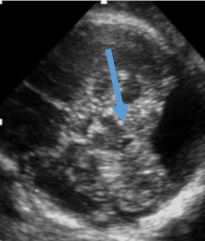

An important observation when faced with this situation is to identify the 4th ventricle as a fluid-filled triangle. In the above three pictures, the 4th ventricle is wide open to the cisterna magna. In the below picture (Figure 4.3) of an arachnoid cyst, the 4th ventricle can still be identified.

Figure 4.3. There cisterna magna is clearly large. Our next step is to attempt to identify the 4th ventricle (blue arrow). If the 4th ventricle does not communicate with the cisterna magna, then you are dealing with a mega cisterna magna or arachnoid cyst.